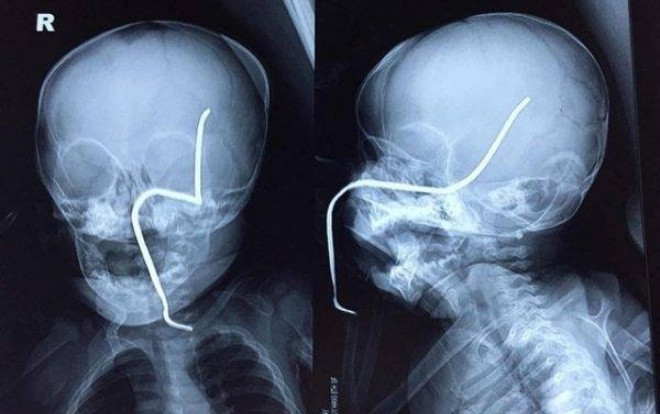

Hình ảnh thanh sắt gỉ văng bắn xuyên má, thủng xương sọ bé gái.

Theo đó, cháu NT.H. (8 tháng tuổi, ở Hà Nội) khi đang chơi ở sân, không may bị chiếc máy đang cắt cỏ cách đó khoảng 15m vô tình làm bắn văng thanh sắt rỉ nằm ẩn dưới cỏ vào má trái, xuyên thủng xương hộp sọ.

Theo bác sĩ Luân, ca mổ khá khó khăn do thanh sắt đâm vào gò má trái qua tổ chức phần mềm của má, đâm thủng sàn sọ, xuyên qua vùng não thái dương và vùng đỉnh sát các mạch máu lớn. Sau hơn 30 phút phẫu thuật, dị vật đã được gắp ra an toàn.